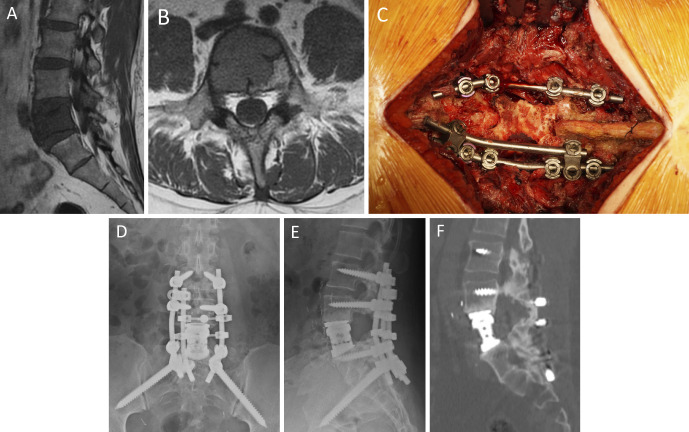

Introduction: In high-grade spinal osteotomy involving large anterior column resection, restoration of the structural integrity of the posterior column at the osteotomy site can reduce postoperative instrumentation failure (IF). This study aimed to describe our technique of posterior strut bone grafting using an en bloc resected vertebral arch, which is useful for posterior column reconstruction after high-grade osteotomies during surgeries for spinal tumor and deformity in the lower lumbar spine.

Technical note: Using a posterior approach, en bloc resection of the targeted vertebral arch was performed in accordance with the surgical technique for total en bloc spondylectomy (TES). The posterior elements in the upper and lower adjacent vertebrae were separated by a significant space after vertebral body resection followed by cage insertion in TES or anterior column osteotomy followed by correction in deformity surgery. To create a new posterior column, the en bloc resected vertebral arch was placed at 90° rotation to bridge the upper and lower vertebral arches. Using this technique, an abundant amount of bone chips made from the resected vertebral elements were placed over the en bloc resected posterior arch as an additional bone graft. The technique was used in three patients who underwent TES for spinal tumors and in one patient who underwent grade 4 osteotomy for adult spinal deformity in the lower lumbar spine. One year after surgery, computed tomography showed that the structural integrity of bony fusion was successfully achieved between the en bloc resected arch and the posterior elements of the adjacent vertebrae in all patients and showed no postoperative IFs.

Conclusions: This bone graft technique created new continuity of the posterior column after high-grade osteotomies in the lower lumbar spine. Bone fusion was achieved in the posterior elements to prevent IF after surgery.